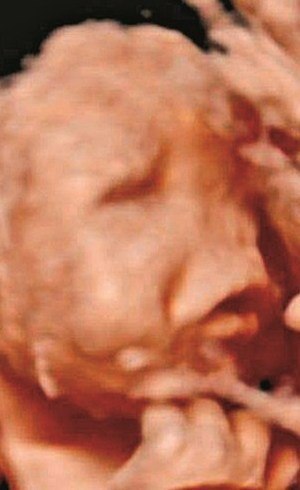

O caso de Rodrigo o bebé que nasceu sem rosto está a ser notícia na imprensa internacional. Um bebé nasceu sem olhos nariz e sem parte do crânio no Hospital de São Bernardo em Setúbal no passado dia 7. Pais mostram bebê que nasceu sem rosto em Portugal Parto aconteceu em 7 de outubro.

Os médicos davam-lhe 24 horas de vida mas na imagem agora revelada no programa da CMTV Rua Segura vê-se um bebé a desenvolver rodeado do. Bebé nasceu sem olhos nariz e parte do crânio depois de a mãe ter realizado três ecografias com um obstetra numa clínica privada em Setúbal que não apontavam qualquer problema. O bebé nasceu sem nariz sem olhos e sem parte do crânio devido à negligência do médico Artur Carvalho que realizou as ecografias de acompanhamento da gravidez sem sinalizar o pais de qualquer problema.

Os pais do beb ê Rodrigo divulgaram sua primeira foto nas redes sociais. Isto distorce completamente a face e o seu caso é o mais grave já registado. Os pais de Rodrigo o bebé sem rosto como ficou conhecido sem olhos nariz e parte do crânio mostram pela primeira vez um foto do filho.

O pequeno ficou conhecido no mundo todo por ter nascido sem rosto. Nasceu a 07 de outubro sem olhos nariz e parte do crânio. Foi esta sexta-feira revelada uma nova fotografia do bebé sem rosto.